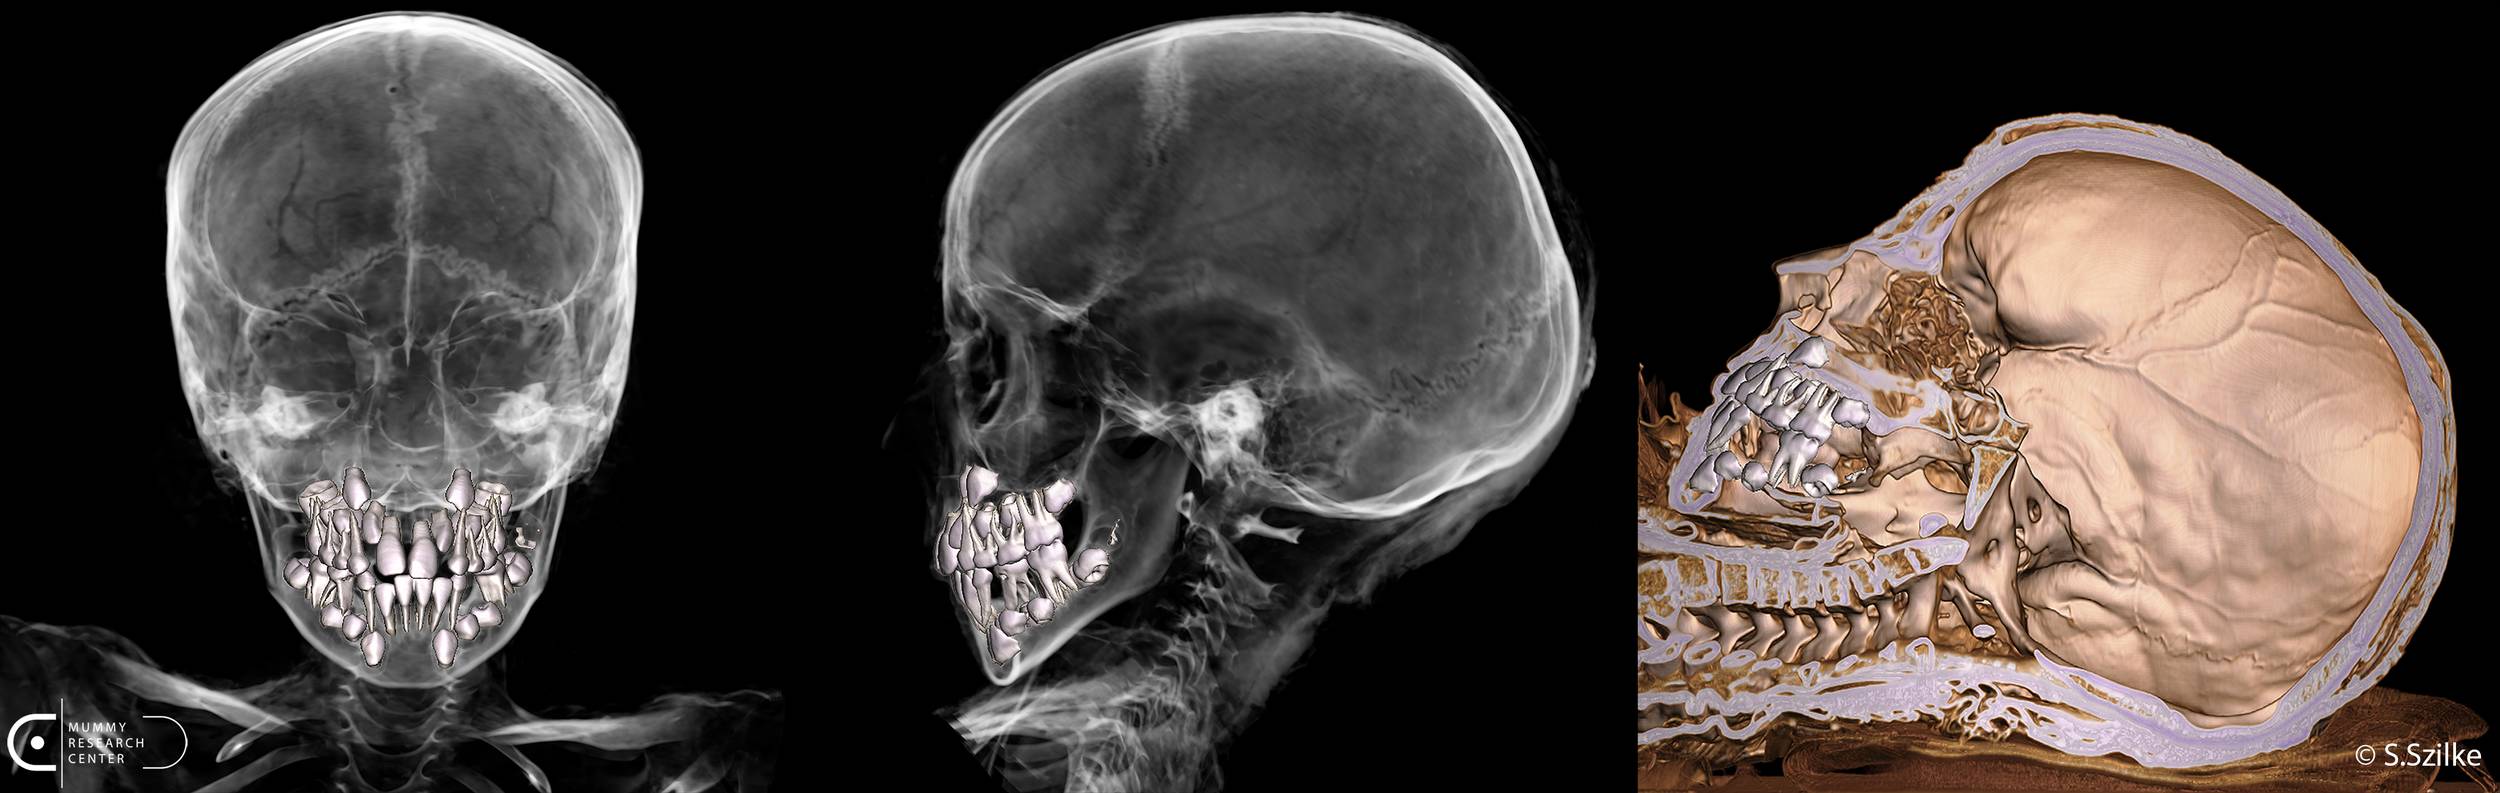

Badania radiologiczne przeprowadzono z użyciem aparatu rentgenowskiego DR GE Optima XR 646 oraz tomografu komputerowego Canon Aquilion Prime ST, czyli jednego z najbardziej zaawansowanych urządzeń tego typu dostępnych w Polsce. Urządzenia te pozwalają uzyskać serię bardzo dokładnych przekrojów ciała, a następnie połączyć je w trójwymiarowy obraz. Dzięki temu naukowcy mogli „zajrzeć” pod bandaże i do wnętrza ciała, nie naruszając ani jednego włókna tkaniny.

Uzyskane obrazy poddano dalszej obróbce w specjalistycznym oprogramowaniu, które umożliwia tworzenie wizualizacji 3D oraz wyodrębnianie poszczególnych elementów, na przykład kości, tkanek czy fragmentów kartonażu. W przypadku mumii nie jest to proste zadanie. Wysuszone tkanki i bandaże nasączone żywicą mają zupełnie inne właściwości niż ciało współczesnego pacjenta, dlatego badacze musieli ręcznie dopasowywać parametry obrazu i krok po kroku oddzielać poszczególne struktury. To żmudna praca, ale dzięki niej można uzyskać znacznie bardziej wiarygodny obraz tego, co kryje się pod bandażami.

Mumia wraz z bandażami i kartonażem ma 123 cm długości. Stan zachowania ciała jest stosunkowo dobry, co pozwoliło na przeprowadzenie wiarygodnych analiz antropologicznych. Na podstawie zachowanych zewnętrznych cech anatomicznych badacze potwierdzili również płeć dziecka, którą przypisywali mu wcześniejsi badacze. W przypadku mumii nie zawsze jest to oczywiste, ponieważ bandaże i elementy kartonażu mogą zasłaniać ciało, a stan zachowania tkanek bywa różny. W tym przypadku jednak cechy anatomiczne pozwoliły jednoznacznie stwierdzić, że był to chłopiec. Wiek w chwili śmierci oszacowano na około osiem lat. Kluczowe znaczenie miała analiza rozwoju zębów, uznawana za najdokładniejszą metodę określania wieku u dzieci, a wnioski potwierdziła ocena stopnia zrastania kości długich. Szkielet zachował się w układzie anatomicznym, bez większych przemieszczeń. Ciało spoczywa na plecach, z rękami wyprostowanymi wzdłuż tułowia i złączonymi stopami.

Badania pozwoliły także odtworzyć przebieg zabiegów mumifikacyjnych. Mózg usunięto przez nos, co potwierdzają zmiany w obrębie kości sitowej i przegrody nosowej. Wnętrze czaszki nie zostało wypełnione dodatkowymi substancjami. W jamie brzusznej nie stwierdzono klasycznego nacięcia w ścianie brzucha. Najbardziej prawdopodobne jest usunięcie narządów wewnętrznych przez odbyt, co odpowiada praktykom znanym z okresu późnego i ptolemejskiego. Wnętrze tułowia zostało częściowo wypełnione tkaniną, natomiast nie stwierdzono dużych ilości żywic czy innych materiałów wypełniających. Obrazy tomograficzne sugerują, że mogły zachować się fragmenty niektórych narządów, między innymi wątroby.